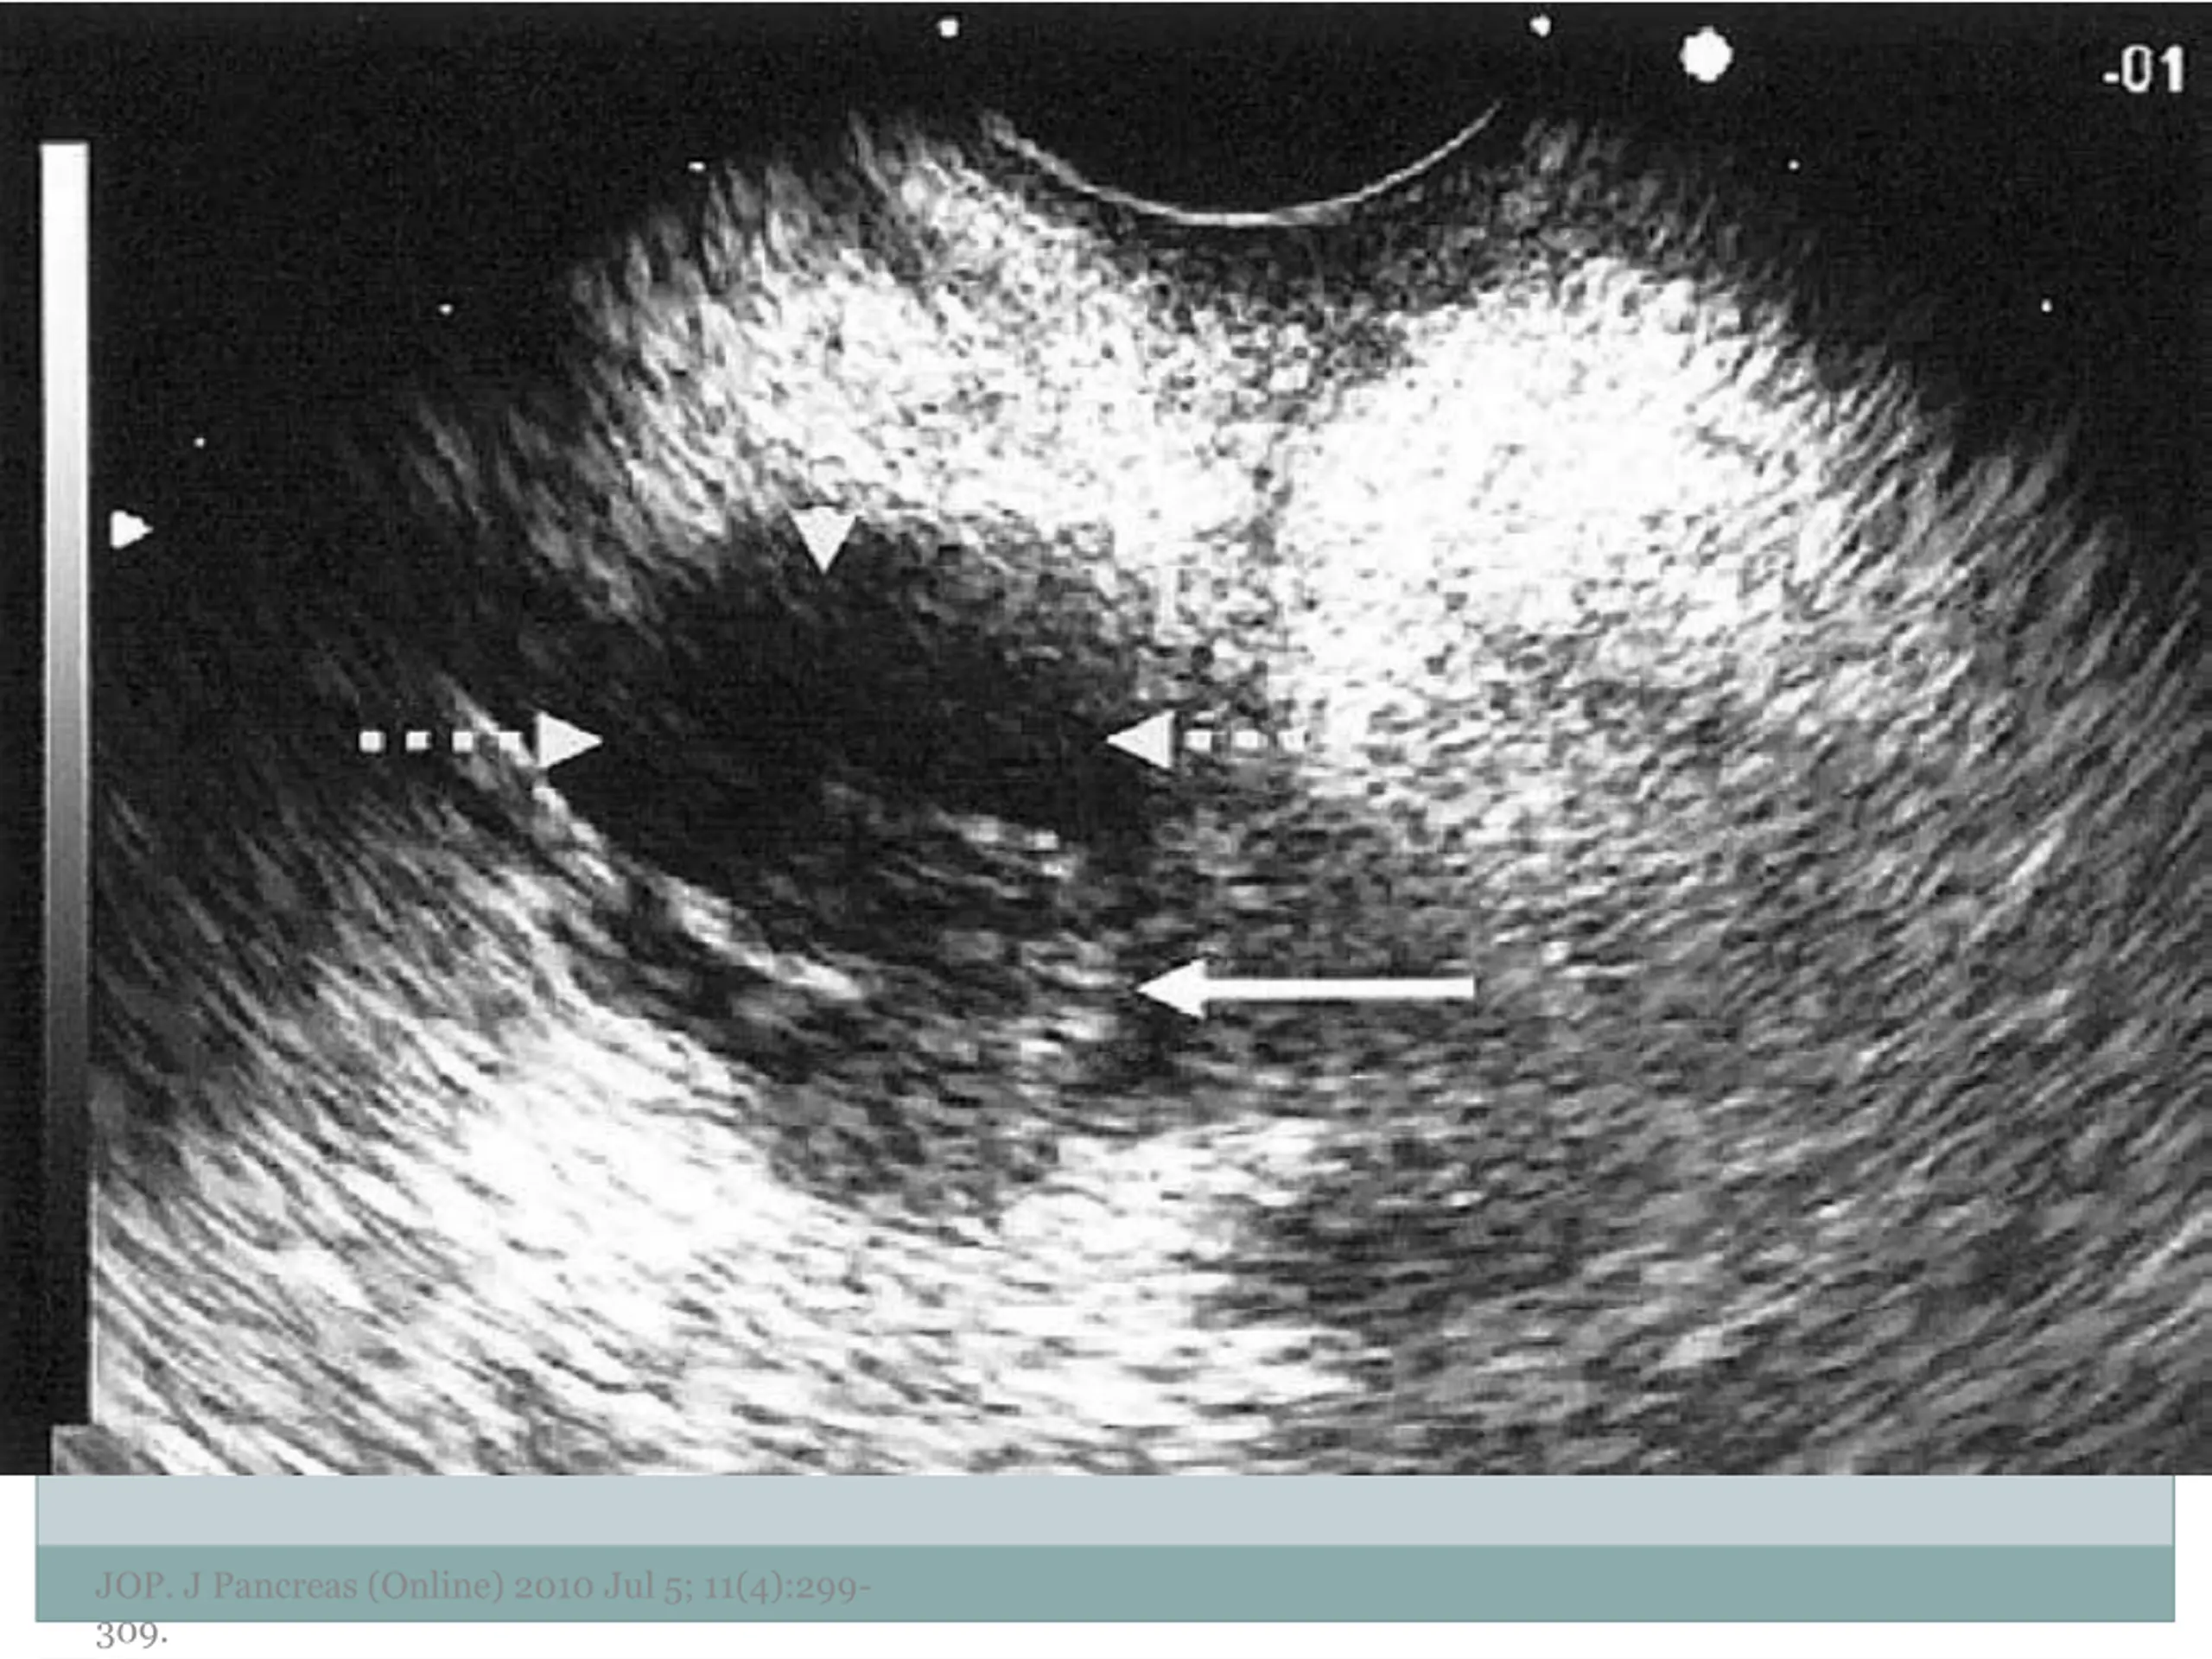

7. EUS Morphology Cyst wall Thick vs. thin Solid component Associated with malignancy Septations Micro vs. macrocystic Ductal abnormalities Main duct vs. side duct Number of cyst Lymphadenopathy EUS morphology can correctly differentiate mucinous from non-mucinous cystic lesions approximately 50% of the time JOP. J Pancreas (Online) 2010 Jul 5; 11(4):299- 309.

10. Examples of Morphology JOP. J Pancreas (Online) 2010 Jul 5; 11(4):299- 309.